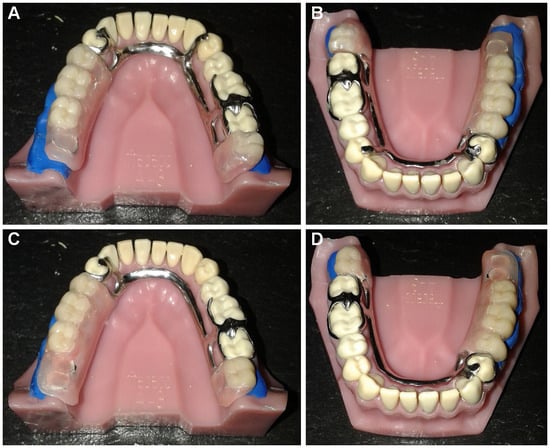

Forces Transmitted to Abutment Teeth in Distal Extension Removable Partial Denture—Impact of Indirect Retention

by Susana João Oliveira, Margarida Sampaio-Fernandes, José Carlos Reis-Campos, Manuel Sampaio-Fernandes, Mário Augusto Pires Vaz and Maria Helena Figueiral

Prosthesis 2025, 7(6), 157; https://doi.org/10.3390/prosthesis7060157 - 3 Dec 2025

Background/Objectives: Stability, retention, and support are removable partial denture (RPD) biomechanical principles. The literature shows contradictory opinions on indirect retention in RPDs, but no solid scientific evidence exists. This in vitro research aims to analyze indirect retainers’ (IRs) influence on forces transmitted [...] Read more.

Background/Objectives: Stability, retention, and support are removable partial denture (RPD) biomechanical principles. The literature shows contradictory opinions on indirect retention in RPDs, but no solid scientific evidence exists. This in vitro research aims to analyze indirect retainers’ (IRs) influence on forces transmitted to abutment teeth of a Kennedy Class I mandibular RPD. Methods: Bilateral distal-extension mandibular RPDs—differing only in the presence or absence of an IR on tooth 44 (IR model vs. nonIR model, respectively)—were installed on an acrylic master model. Tensile forces were applied perpendicularly to the occlusal plane on the longest free-end saddle’s distal aspect. Electronic speckle pattern interferometry (ESPI) measurements were obtained with and without an IR. The three-dimensional out-of-plane displacements of both models were acquired. Results: Abutment teeth 46 and 47 contralateral to the longest distal extension suffered more deformation under displacement forces when an IR was used. In turn, the IR’s influence on the deformation values of the abutment tooth 34 adjacent to the larger edentulous area depended on the intensity of the tensile force exerted: low-intensity forces resulted in reduced deformation, while higher-intensity forces resulted in higher deformation. Conclusions: This study’s findings indicate that indirect retention promotes better tensile force distribution in the existent teeth. However, they also question the IR’s role in protecting abutment teeth against excessive torque forces. This study’s preliminary results highlight the need for research on indirect retention principles using new methodologies, namely, in silico and ex vivo studies, and their experimental and clinical validation. Full article